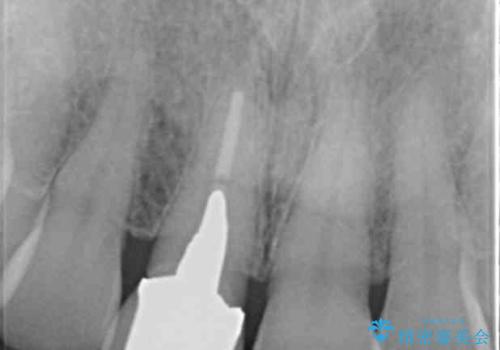

- 十数年前に治療した前歯のクラウンの歯ぐきの位置が変化し、黒いラインが見え審美性の改善を求めて来院されました。

ファイバーコアのやりかえを行ったのち、金属を用いないジルコニアクラウンによる再補綴を行い前歯の審美性の向上を計画します。